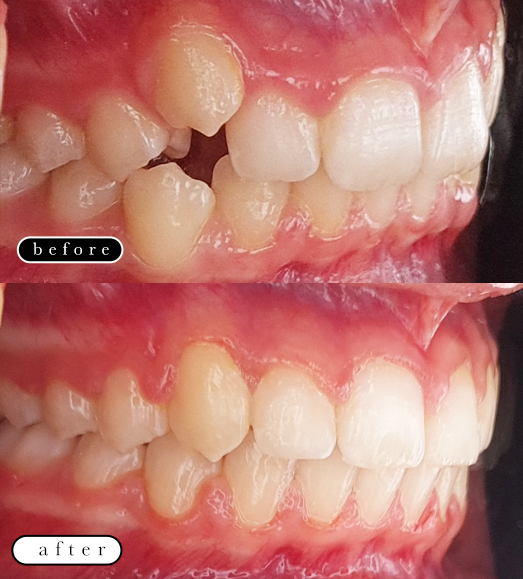

O našoj kvaliteti najbolje govore naši rezultati!

Centar za ortodonciju Petra Džapo